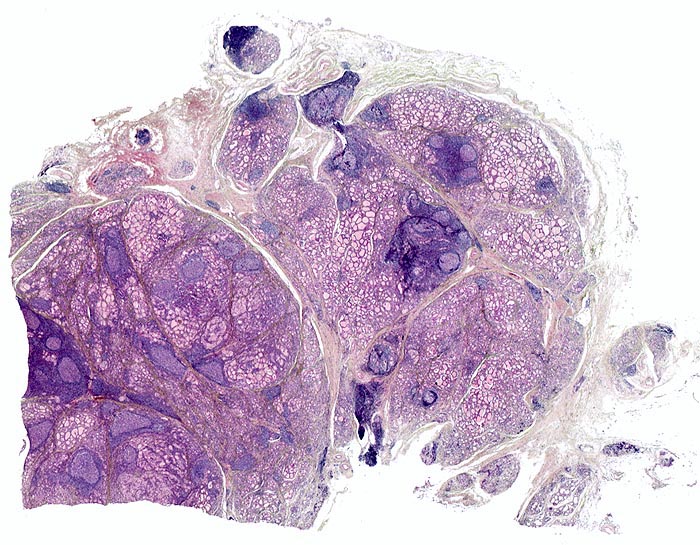

chronische lymphozytäre Thyreoiditis Hashimoto

Bei kleiner Vergrösserung fällt eine angedeutet knotige Struktur des Gewebes auf. In diese knotige Grundstruktur eingebettet sind immer wieder dichte Infiltrate von Lymphozyten und Plasmazellen («blaue Herde») und eindeutige Lymphfollikel mit Keimzentren. Es besteht eine geringe Parenchymfibrose.